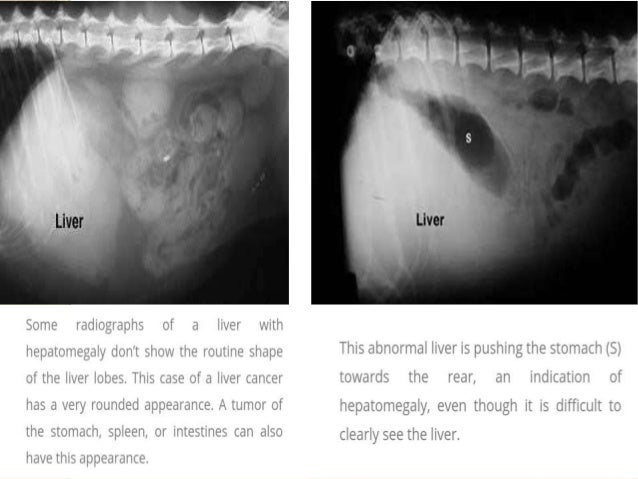

Diagnosis Of Liver Disease In Dogs & Cats

www.slideshare.net